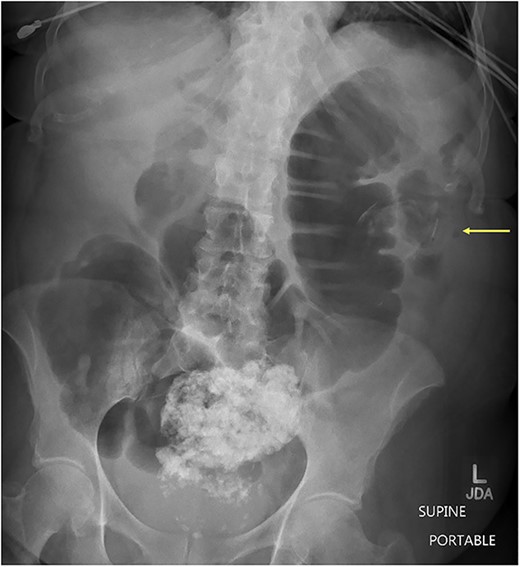

Case presentation # 1: An 80-year-old female with congestive heart failure and hypertension, presented to the emergency room with 4 days of diffuse abdominal pain associated with nausea, vomiting and anorexia. She was hemodynamically stable upon presentation, with upper abdominal tenderness on exam. Initial imaging (Figs 1 and 2) was obtained, showing a CCF with large bowel obstruction caused by an 8-cm gallstone in the descending colon. The patient was taken to the operating room for an exploratory laparotomy, where upon inspection a large gallstone in the descending colon and a fistulous communication between the gallbladder and hepatic flexure of the colon were noted. Takedown of the fistula was attempted, however because of extensive colonic involvement a decision was made to perform a right hemicolectomy with primary anastomosis, as well as a partial cholecystectomy at the level of infundibulum due to chronic inflammation and thickening of the gallbladder. The gallstone was taken out with the specimen (Fig. 3). The postoperative course was significant for exacerbation of heart failure, but ultimately, she was discharged home upon successful tolerance of a regular diet with return of bowel function.

CT of abdomen and pelvis showing an inflamed gallbladder with fistulous communication within the hepatic flexure of the colon. Large descending colon enterolith (4.5 × 4.3 × 8.0 cm). Apparent pneumobilia.